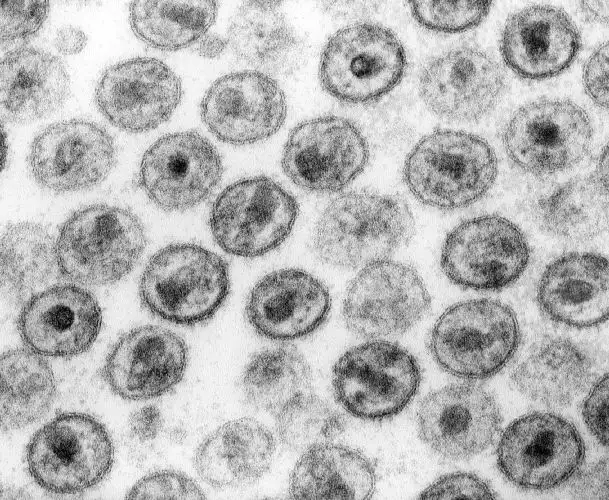

这种疾病的名字是获得性免疫缺陷综合征,更广为人知的名字是艾滋病。它的病原体是一种叫做人类免疫缺陷病毒的微小病原体。这种病毒的大小只有红细胞的十万分之一,肉眼完全无法看见。但它所携带的遗传信息却足以摧毁人体最精密的防御系统,将一个健康的成年人变成一具活着的空壳。

HIV的复制速度惊人地快。一个被感染的细胞每天可以产生数千个新的病毒颗粒。在没有治疗的情况下,人体每天可以产生多达一百亿个新的病毒颗粒。与此同时,HIV的逆转录酶极其容易出错,平均每次复制都会引入新的突变。这种高突变率使得病毒能够快速进化,逃避人体的免疫反应和药物的作用。

尽管鸡尾酒疗法取得了巨大的成功,它仍然不是一种治愈方案。患者必须终身服药,一旦停药,病毒就会卷土重来。这是因为HIV有一个叫做病毒储存库的秘密武器。在感染的早期,一些病毒会将自己的基因整合到休眠的免疫细胞中。这些细胞不活跃,因此不会产生新的病毒颗粒,也不会被药物杀死。但它们携带着病毒的遗传蓝图,随时准备在条件成熟时重新激活。

这个储存库的存在使得彻底清除HIV成为几乎不可能的任务。科学家们估计,即使是最敏感的检测方法能够检测到的最低病毒载量,也意味着体内仍有约十万到一百万个潜伏感染的细胞。这些细胞可以存活数十年,在患者停止治疗后迅速重启感染过程。